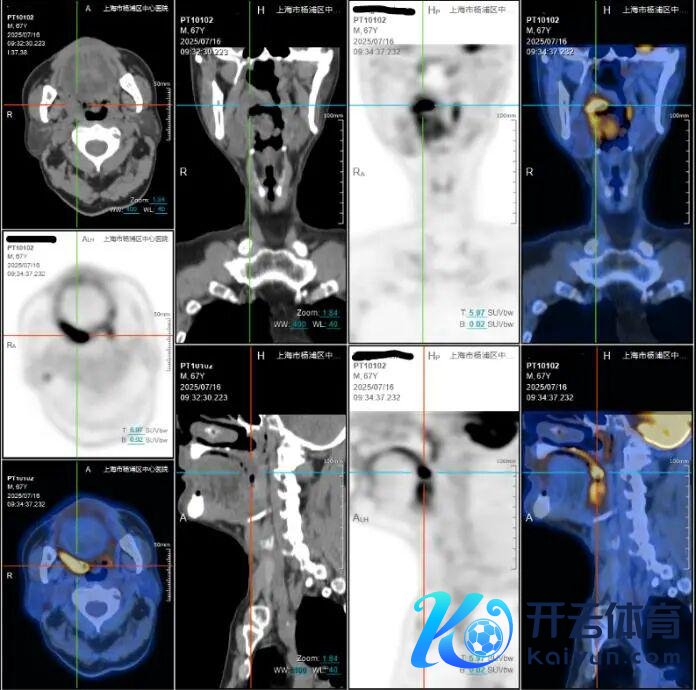

王老伯化疗前PET-CT

(十字线交叉处为肿瘤)

为了缩小手术风险,改善患者体验,徐亚平主任团队决定初始个体化的新接济化疗决策,借助化疗技巧先缩小肿瘤体积。历程一个月的化疗,养息恶果权贵。影像明晰地泄露肿瘤彰着萎缩,规模大幅减小!这为后续根治手术争取了关节的窗口期,为原来难度极高的根治手术创造了厚爱契机。